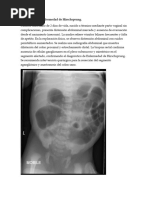

Las pruebas radiológicas incluyen una RSA (radiografía simple

de abdomen) y un enema opaco. Si el estado del niño lo

permite, estas pruebas deben realizarse antes de cualquier

maniobra de descompresión (sondeo y enema evacuante) para

tener mayores oportunidades de visualizarla zona transicional.